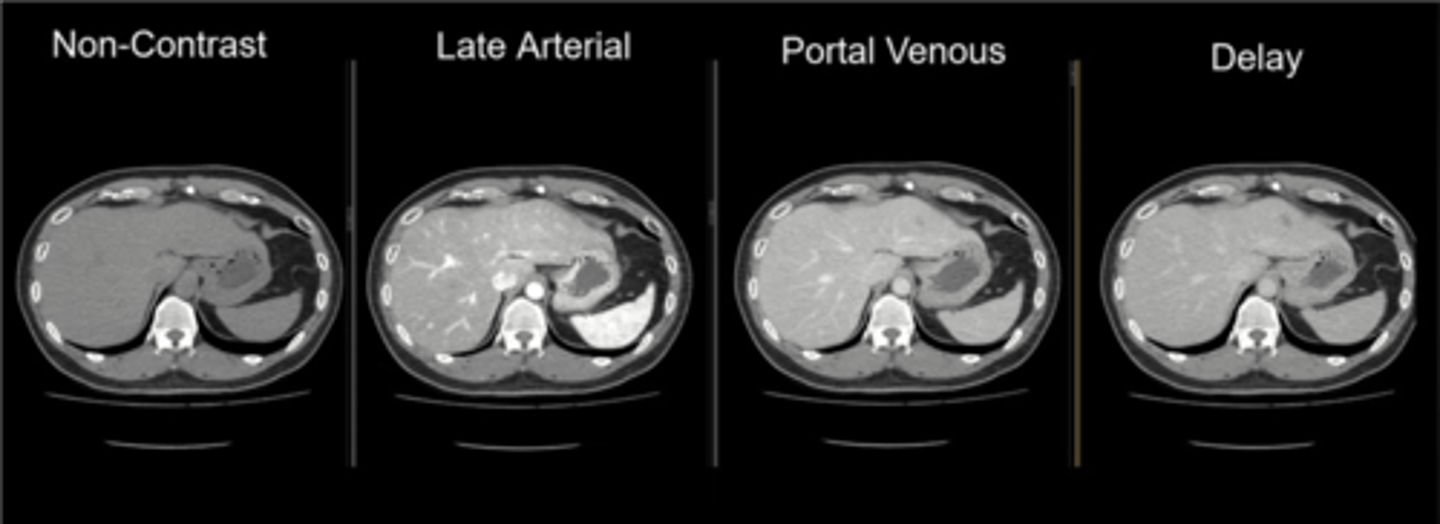

IV contrast timing